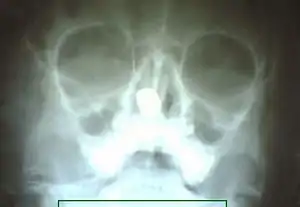

| Xray of paranasal sinuses showing rhinolith | |